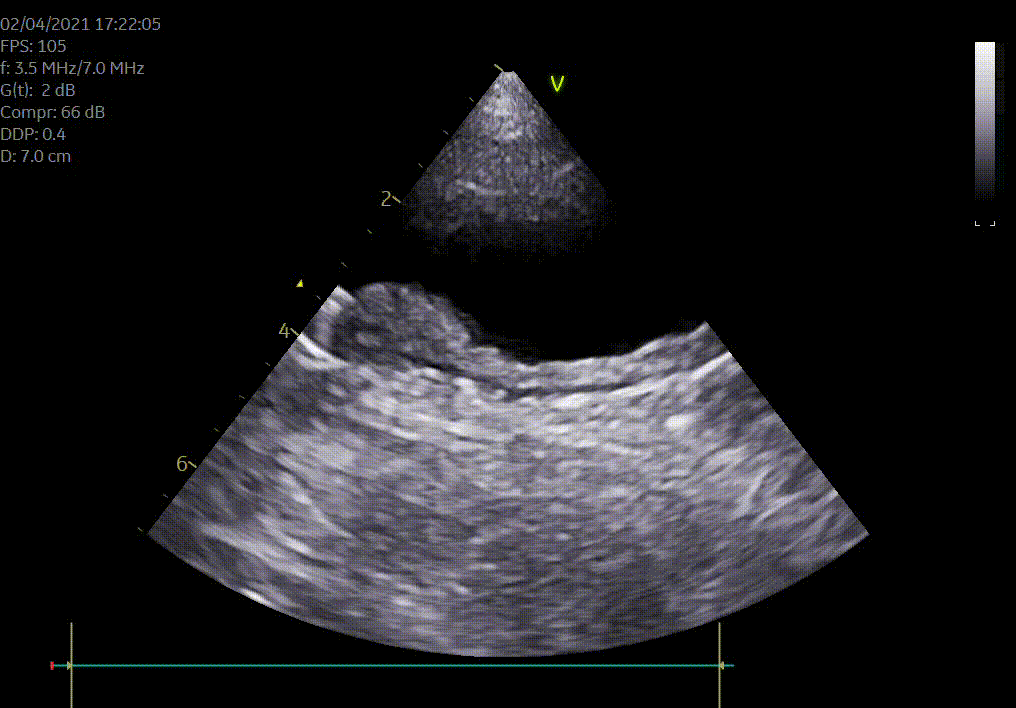

Heeft uw hond of kat een hartruis? Het is dan aangewezen om een echocardiografie (hartfilmpje) uit te laten voeren om na te gaan of er best ondersteunende hartmedicatie moet opgestart worden. Met een echocardiografie gaan we na of het hart normaal gevormd is, normaal werkt en beoordelen we de ergheidsgraad van eventuele kleplekken.

Hartonderzoek - Echocardiografie - Electrocardiografie (EKG) - Radiografie

Waarom een echografie laten uitvoeren? Echografie geeft een goed beeld van de inwendige organen zoals het hart, de longen, de maag en darmen, de milt, de lever, de galblaas, de nieren, de blaas, de baarmoeder...Met echografie is een drachtcontrole (zwangerschapscontrole) bij een kat vanaf 18-21 dagen en bij een hond vanaf 28 dagen mogelijk.

De kwaliteit van een echografie is afhankelijk van de lichaamsbouw en de mate dat je hond of kat meewerkt.